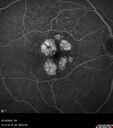

77 year old female HPI: CC: Decreased Vision OU. Since Last Visit: worsening. Location: central vision. Context nset/Aggravation: while reading. Modifying Factors: when closes one of her eyes notices letters are missing. Duration of Problem: couple of months. Associated Symptoms: foggy circle temporal when driving OU. Severity: moderate. Course: intermittent . HPI obtained by Steven M. Cohen, MD, FACS Medical Hx: Hypertension, Systemic. Hyperlipidemia. Depression. Spinal Stenosis. Psoriasis. Osteopenia Systemic Meds: TIZANIDINE HCL. TRAMADOL HCL prn. ZOLPIDEM. HYDROCORTISONE. TRAZODONE HCL, Clobex 0.05 % Topical Spray. VA OD 20/32, OS 20/20 IOP 13 OU